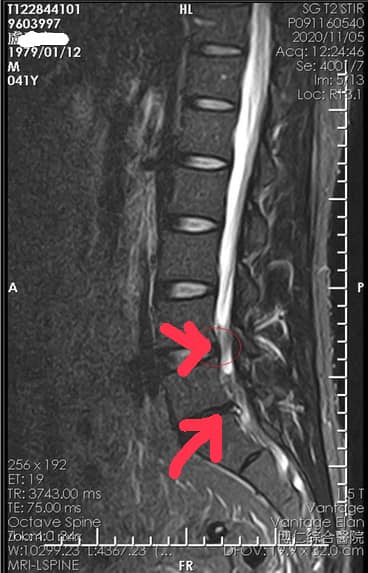

Cervical Spine Treatment Cases 腰椎治療案例 #腰椎手術失敗綜合症候群 #術後沒保養還是又繼續椎間盤突出 #感謝台北梁小姐熱情見證 ... 2021.03.02 #超感動醫案感謝中壢姚阿姨見證 #原本已經坐輪椅的人生看到一絲希望 #脊刻救援牛轉乾... 2021.02.22 #感謝新北中和區陳大哥熱情見證 #從北到南看過眾多中西醫民俗療法 #腰痛到連躺跟坐都... 2021.02.17 #感謝桃園龜山蘆先生熱情見證 #腰椎跟屁股痠痛超過十二年 #腰椎纖維環裂隙導致神經根... 2021.02.16 #騎馬摔傷腰椎醫案 #感謝內湖陳先生熱情見證 #椎間盤突出合併輕微椎間孔狹窄 #重新騎... 2021.02.03 #巨大椎間盤突出醫案 #脊椎整合中醫微創逆轉勝 #感謝三峽林先生熱情見證 #為何突出的... 2021.01.29 #腰椎粉碎性骨折手術後調養醫案 #坐輪椅的人生終於看到希望 #脊椎手術失敗症候群 #Fai... 2021.01.26 #感謝台中市大肚區患者熱情見證 #第二次治療腰痛好超多 #腰酸痛時間快一年了 #親筆寫... 2020.12.05 #腰椎嚴重滑脫醫案 #原本左腳麻痛無法久站超過十分鐘 #脊椎整合中醫微創療法逆轉勝 #... 2020.12.02 #感謝林口楊先生熱情見證 #椎間盤整和中西醫微創療法逆轉勝 #曾經大痛到無法走路嚴重... 2020.11.25 #今天來聊巨大骨刺為何可以吸收回去! #椎間盤突出需要多久才能吸收呢? #馬尾神經症候... 2020.11.10 #腰椎滑脫一定要開刀嗎? #骨科認為開刀置放骨釘穩定錐體 #如果患者可以藉由增強肌... 2020.11.04 #六年的長期腰酸痛醫案 #原來是椎管狹窄合併輕微突出 #每年冬天準時發作苦不堪言 #感... 2020.10.31 #椎管狹窄案例 #感謝新莊陳大哥熱情見證 #腰酸痛數年原來是椎管狹窄 #來診前已經痛到... 2020.10.28 #知名四代魚丸店掌門人熱情見證 #腰椎中醫微創逆轉勝 #椎間盤突出醫案 #感謝新北... 2020.10.23 ← 上一頁 8 9 10 11 12 下一頁 →